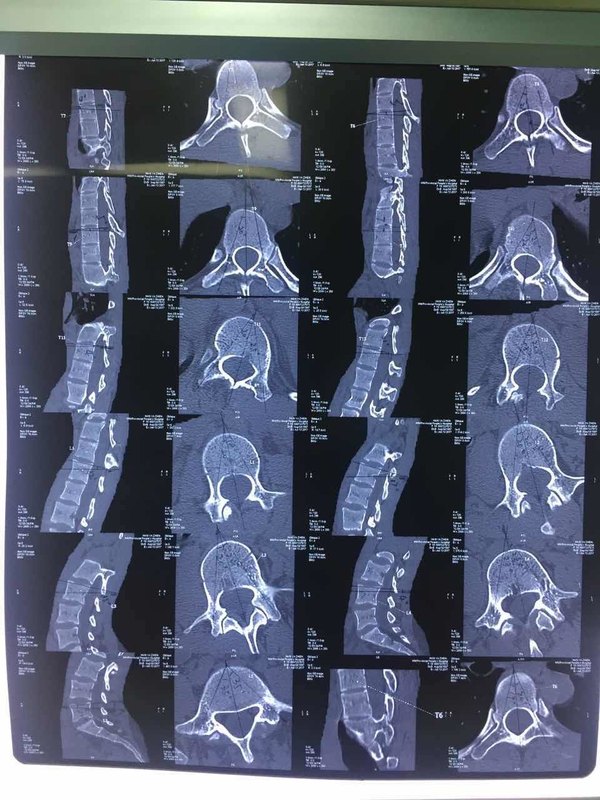

僵人综合征是一种罕见的疾病,其特征为累及中轴肌(颈椎或腰椎旁的肌肉)的进行性肌肉僵硬、强直及痉挛,从而导致行走功能严重受损。现在多认为僵人综合征与自体免疫机制异常有关,常和一些自身免疫性疾病包括甲状腺炎、白癜风、恶性贫血及1型糖尿病等同时出现。口安定可作为最佳初始治疗选择;若治疗效果不佳,也可改用或加用巴氯芬治疗。肉毒素并非能治愈僵人综合征,但是它能明显减轻患者的肌肉痉挛症状、减少疼痛、提高生活和工作能力、改善睡眠质量,同时也能明显缓解颈椎或腰椎旁板状般强直肌肉的僵硬。典型的僵人综合征患者,表现为背部肌肉板状强直,治疗重点是椎旁表层竖脊肌。通常需双侧多点注射;每次注射总量为200~300U。当然若累及颈肩部或四肢肌肉时,需另外根据具体情况进行评估治疗。注射治疗后数日至2周左右起效,建议注射后2~4周复诊以评估注射方案是否恰当;疗效维持3~6个月,可再次注射;注射前已使用药物一般可继续使用,在肉毒毒素起效后可根据残留症状调整剂量;尽量避免诱发痉挛的因素,如突然运动、噪音影响或情绪波动等。